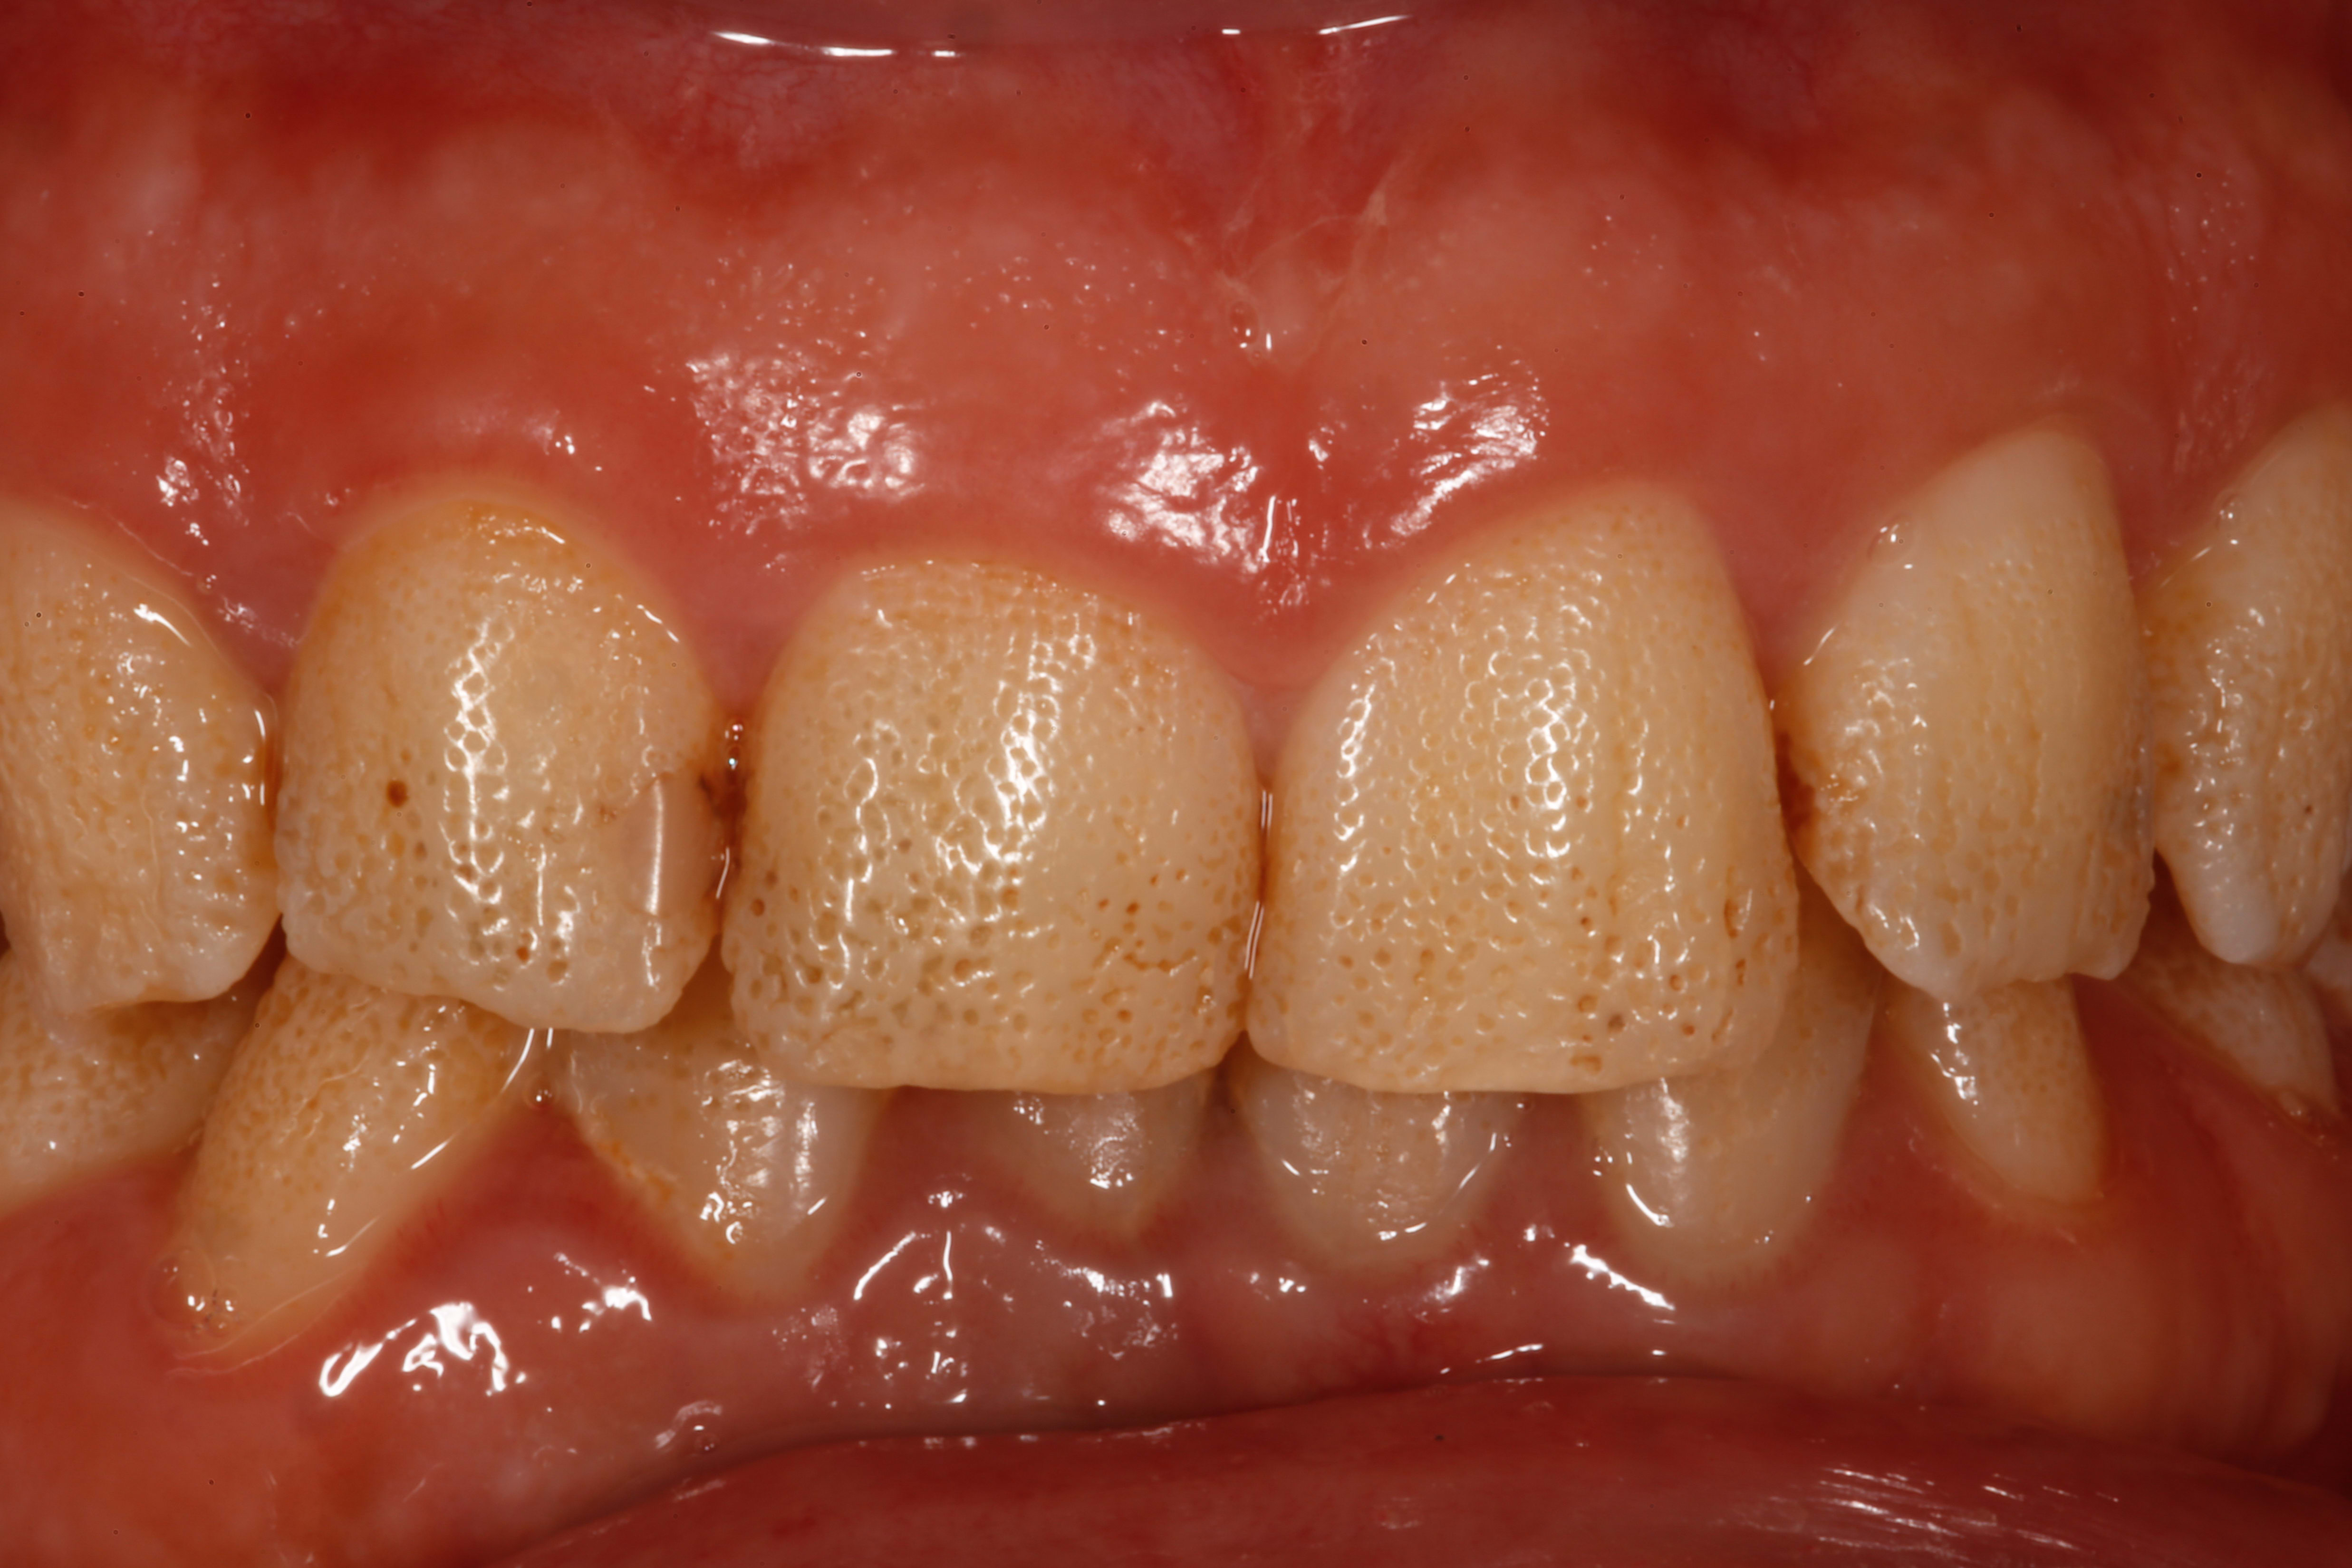

Là je cale... Je suis tombé sur ce sourire chez une patiente de 30 ans, pas de problème de santé notable, et j'ai eu beau chercher pendant l'interrogatoire ou dans les bouquins une raison pour expliquer cet aspect grêlé de l'émail, j'en ai pas trouvé une seule !

Toutes les dents définitives sont concernées, émail vestibulaire comme palatin. Ca a toujours été comme ça dans les souvenirs de la patiente.

Amélogenèse imparfaite hypoplasique ponctuée, yu as une photo comme ça dans l'article de l'ID du 7 juillet 2021

Plutôt amélogenèse imparfaite effectivement, la fluorose donne des colorations plus marquées et des pertes plus étendues dans les stades graves; pas cet aspect pointillé qui est extrèmement régulier.

C'est bien la génétique, et l'amélogénèse imparfaite ici (prévalence 1/14 000, pas de chance), dans sa variante hypoplasique ponctuée (pas la plus discrète)

Ci joint la photo de l'article de l'information dentaire dont parlait Chic22, issu de l'article des Drs Xavier BONDIL et Gabriel DOMINICI. (Les modos, si joindre la photo pose souci, je la supprime...)